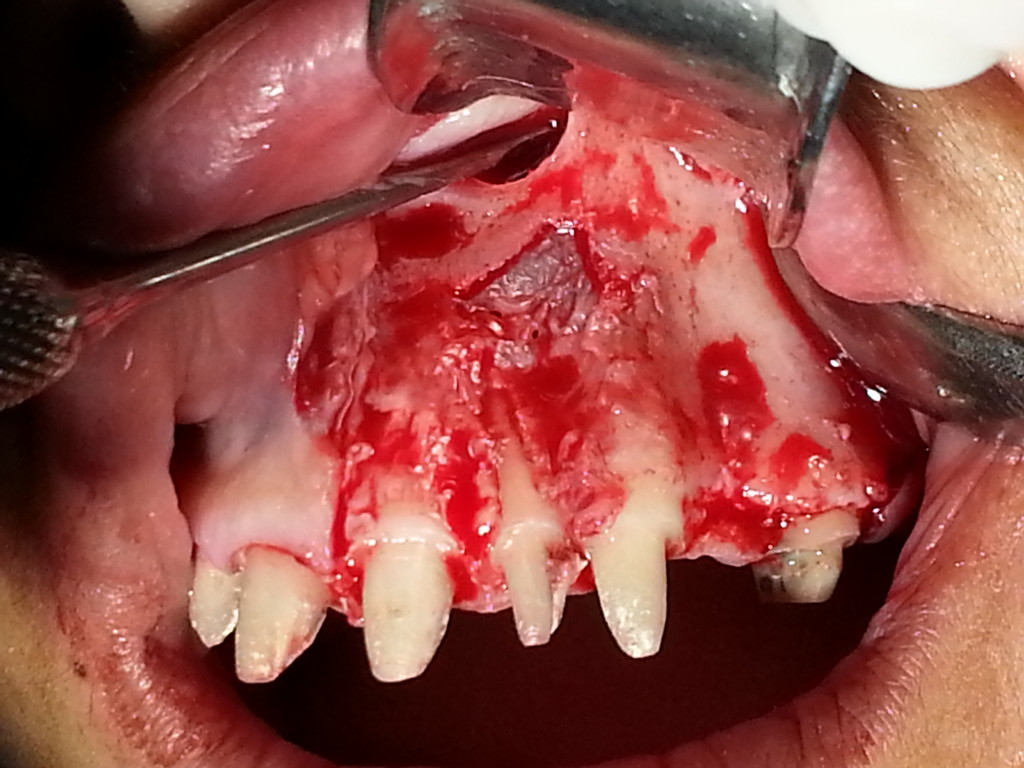

EXTRACCIÓN DE CANINOS RETENIDOS.

CASO CLÍNICO. APICEPTOMÍA Y QUISTECTOMÍA EN LA PREMAXILA.